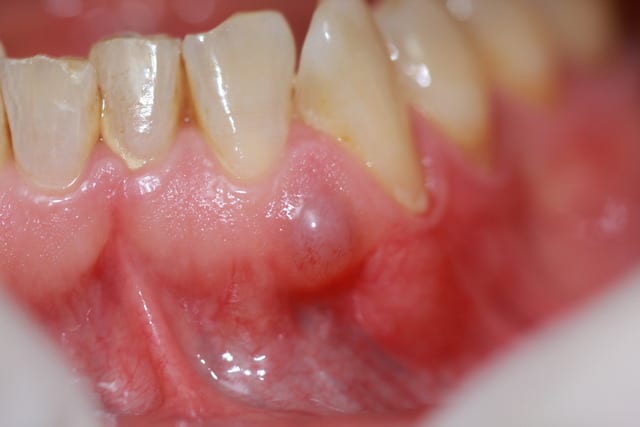

Patient de ma collaboratrice, la soixantaine, pas de pbs de santé particuliers. J'aurais dit parulie. Selon vous quel est le dg et quelle est la CAT?

L´aspect translucide me fait penser a un mucocéle.Par contre je ne sais pas si ça peut se produire sur la gencive attachée.Je les ai toujours vu sur le revers de la lévre.

Jai aussi pensé a un kyste mucoide/mucocèle.

Si "parulie": pb paro ou endo sur.dents voisines ?

Ça ressemble en effet à un mucocèle mais éffectivement la localisation me semble douteuse..